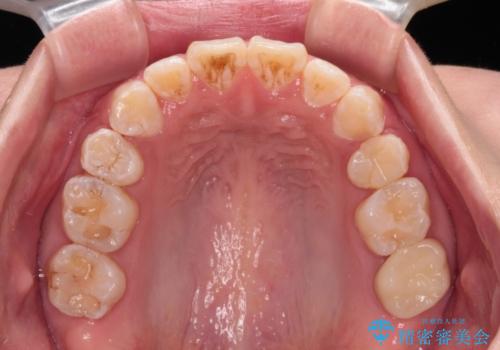

- 前歯のクロスバイトと、口元が閉じにくいとのことで来院された患者様です。

口元の突出感を改善する必要があるため、上下左右の第1小臼歯4本を抜歯し、ワイヤー装置にて矯正治療を行うこととしました。

むし歯のリスクが高かったため、治療が長期化しないように心がけました。

当初の予定通り、2年強で無事に治療を終えることができました。